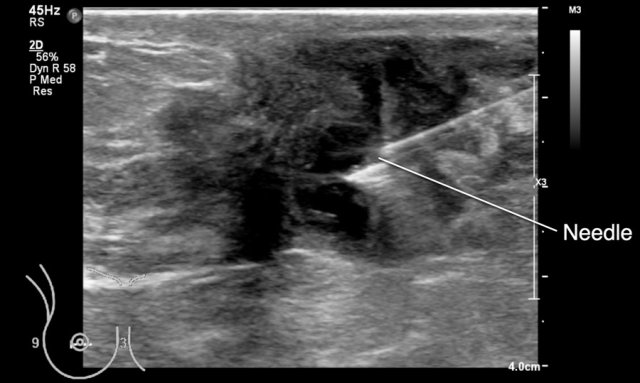

Subsequently the abscess was apirated.

Aspiration is the first choice treatment of abscesses.

No need for surgery or antibiotics in this case, although antibiotics are sometimes also given.

Here another abscess located behind the nipple, which was aspirated.

This can be a painful procedure.

It is best to inject local anesthesia in the skin and subcutis and to try to drain the pus through that same needle.

If the pus is too thick, a thicker needle will do the job.

Take some time for the local anesthesia to work.